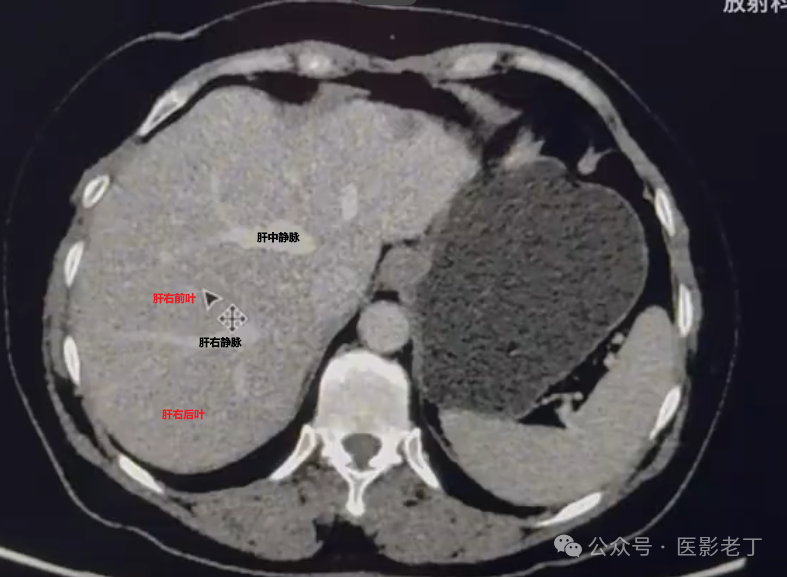

第四步、找肝右静脉,分肝右前后叶。肝右静脉为界,前方为肝右前叶,后方为肝右后叶。

第五步、找门静脉右支,分肝右叶上段和下段.门静脉上方的为上段,及S7、S8段;门静脉下方为下段,即S5、S6段

总结:1、胆囊和下腔线分肝左右叶;2、镰状韧带分左叶为内外叶;3、门静脉左支分肝外叶为S2 S3段,上2下3;4、肝右静脉分肝右叶为前后叶;5、门静脉右支分肝右叶上下段。